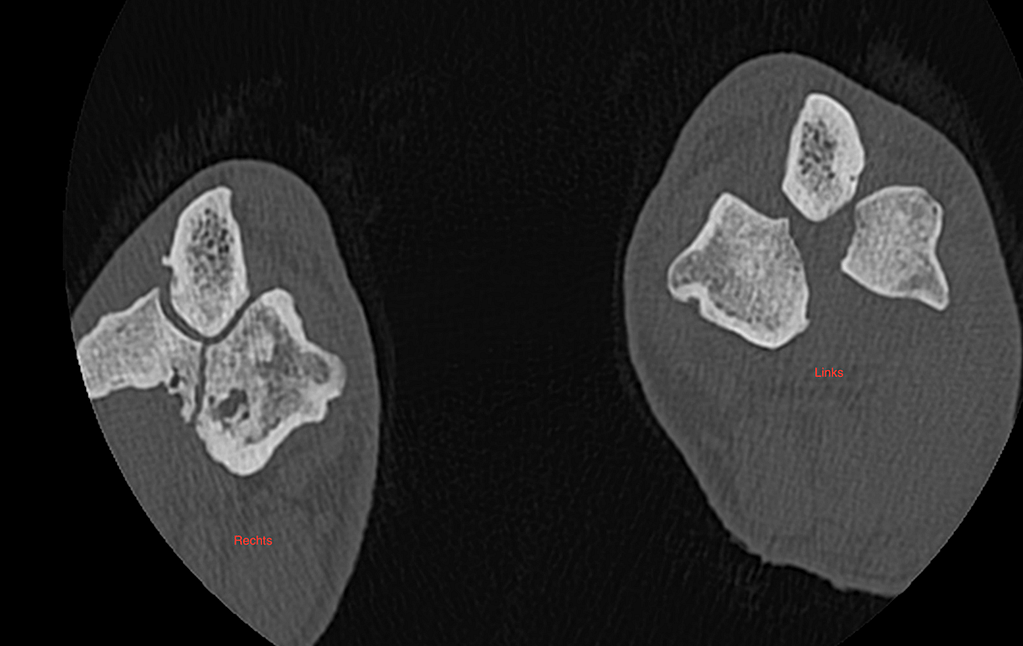

Zoals klinisch reeds verdacht is de fissuur in de linker elleboog geëvolueerd naar een totale fractuur. In de rechter elleboog is ook een duidelijke fissuur lijn zichtbaar.

Fig. 2: Rechter elleboog vertoont een fissuur zonder verplaatsing intercondylair. In de linker elleboog zijn beide condylen van elkaar losgeslagen.